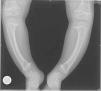

Se presentan 2 casos clínicos de niños con raquitismo carencial. Caso 1: niña de 20 meses remitida a las consultas de Traumatología y Pediatría por genu varo. En cuanto a sus antecedentes, sus padres proceden de Marruecos, recibía lactancia materna y presentaba diversificación alimentaria no reglada. No toma profilaxis antirraquítica y escasa exposición solar. Desarrollo ponderoestatural y psicomotor correctos. En las pruebas complementarias destacan: hormona paratiroidea intacta (PTH-i) de 406pg/ml; calcio de 9,4mg/dl; magnesio de 2,2mg/dl; fosfato de 4mg/dl; fosfatasa alcalina de 649U/l y 25-hidroxicolecalciferol (25-[OH]) vitamina D de 6ng/ml (15 a 60ng/ml). En la radiología se observan el ensanchamiento y la irregularidad de las metáfisis del fémur distal y la tibia proximal y distal, con marcado aumento de la incurvación de la tibia bilateral. Las metáfisis tibiales se encuentran deformadas, con el borde afilado en los extremos mediales. Las metáfisis distales del cúbito y el radio son irregulares (fig. 1). Caso 2: niño de 8 meses de origen magrebí que acude a Urgencias por crisis comicial. En la analítica se detectan un calcio de 5,3mg/dl, magnesio de 1,6mg/dl y fosfato de 3,6mg/dl. Había recibido lactancia materna exclusiva hasta los 6 meses y no toma profilaxis antirraquítica. Radiográficamente se observa un agrandamiento de las metáfisis del fémur, húmero y radio en forma de copa, con desflecamiento metafisario (fig. 2). Al completar el estudio analítico encontramos una PTH-i de 463pg/ml y 25-(OH) vitamina D de 8,3ng/ml. En ambos casos se indica tratamiento con vitamina D, ingesta adecuada de calcio y exposición a la luz solar, con buena respuesta y evolución.